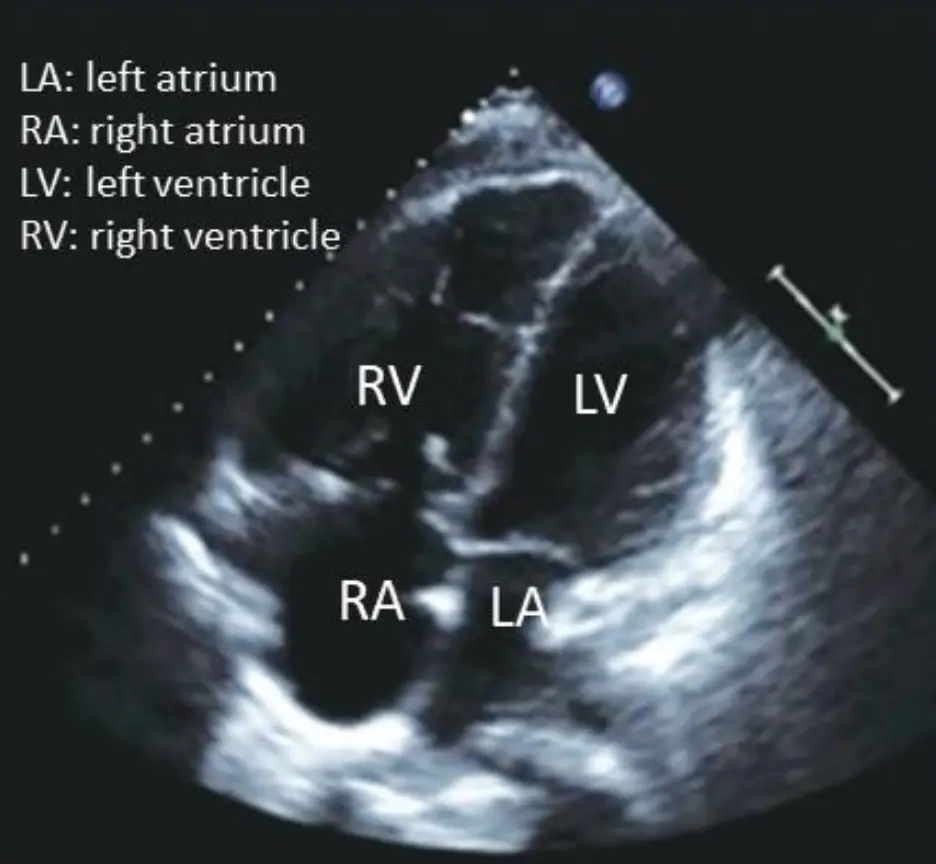

B心臟超音波的影像(如附圖)

附圖為apical four-chamber心臟超音波影像。可見:

- 右心房(RA)與右心室(RV)明顯腔室增大,遠大於對側左心房(LA)及左心室(LV)。

- 室間中隔平坦或向左心室鼓出,造成左心室橫截面呈“D形”,提示右心室壓力顯著升高,符合肺動脈高壓時RV壓力負荷的典型回聲圖像。 (pmc.ncbi.nlm.nih.gov)